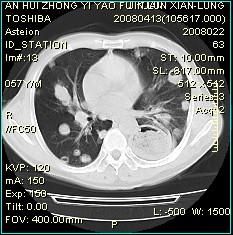

神經性頭疼的試驗室檢查一般不會有問題,本身屬於功能性疾病,大腦的檢查如顱腦CT、磁共振、腦電圖、腦彩超、腦脊液等都是正常的。大多數病人腦彩超檢查會有腦供血不足的現象,但這些是短暫性或可逆性的,是由於頭頸部肌肉痙攣壓迫血管造成的一過性現象。神經性頭疼病史比較長的病人腦部檢查不是不可以的,做個腦部CT檢查也是必須的,可以排除腦瘤或其他器質性病變,多次重複檢查不僅花費大量資金,造成病人經濟負擔,而且會對人體造成放射性傷害。